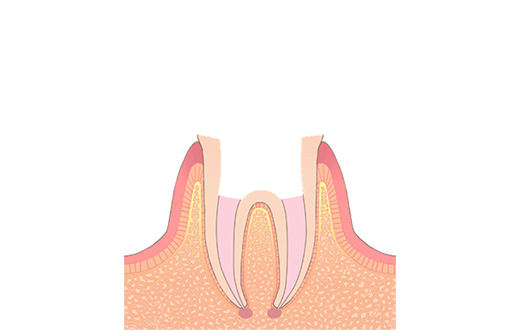

C3重度う蝕

エナメル質、象牙質を貫通し、歯髄(歯の中にある神経や血管)まで到達した虫歯です。急性症状がある場合は、鼓動に連動したような痛み(拍動痛)が現れ、特に夜になると眠れないほどの痛みが出ることがあります。すぐに根管治療が必要です。